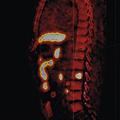

Pour les récidives biologiques après traitement local

Dans certaines circonstances particulières (progression rapide du PSA), une SA androgénique peut être indiquée. Elle conduit parfois à une résistance à la castration, justifiant la prescription d’HTNG. Dans ce contexte, on réalise régulièrement une tomographie par émission de positons (TEP ; figure ) marquée à la fluorocholine, qui localise dans plus de 80 % des cas le site de la récidive et permet un traitement adapté à celle-ci.